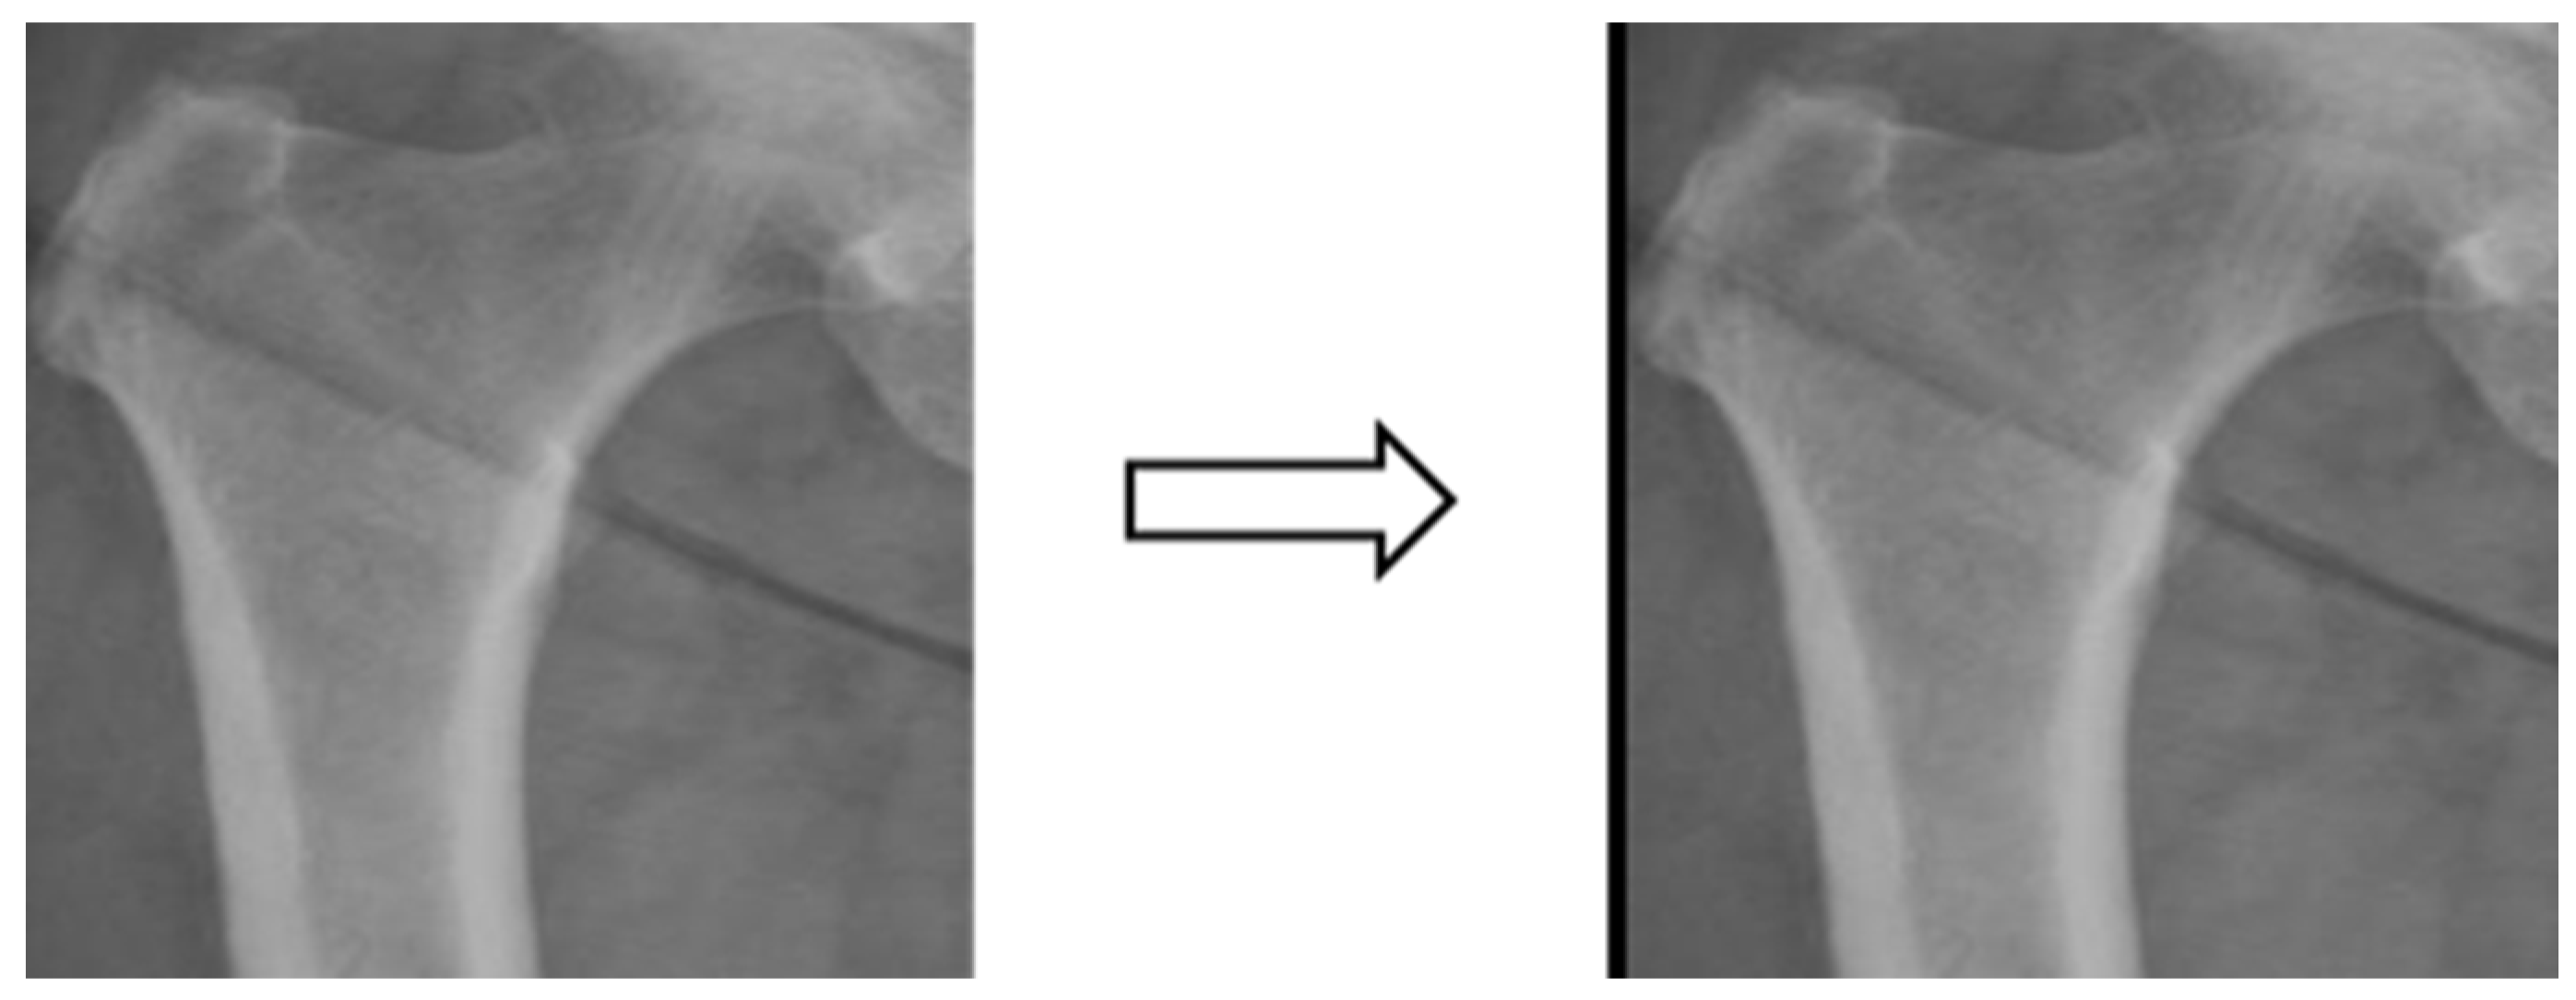

3.3.4. Data Augmentation

In this study, the X-ray image data were insufficient for image classification experiments. Training the model with the original dataset could lead to issues such as model underfitting and poor generalization due to the low complexity of the model and the limited image features. Therefore, the dataset consisting of X-ray images from four different body areas was augmented by applying transformations like rotation (e.g., Figure 5), shifting (e.g., Figure 6), and random scaling (e.g., Figure 7). Importantly, these augmentations were performed without altering the bone contour morphology, background, or color. The purpose of data augmentation was to aid in the training of deep learning models [30]. Additionally, data augmentation serves to address underfitting problems in classification experiments and can potentially enhance experimental accuracy if overfitting issues arise in the future [31]. Table 1 presents a comparison of data volume before and after data augmentation.

After data expansion through rotation and shifting, each part is expanded by seven times the amount of data, and after expansion, a random scaling method is added so that each batch of data is randomly scaled by between −20% and 20% to achieve the effect of increasing data plurality.